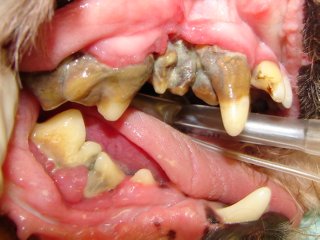

In stage III (established periodontitis) the gum lining starts receding. The bone loss is getting worse and roots are being exposed.

In stage IV (severe periodontitis) there is severe gum recession, bone loss and root exposure. The periodontal supporting structures are almost entirely destroyed and the teeth are mobile. Bacteria may be spreading throughout the entire body via the bloodstream and may damage the kidneys, liver and heart.